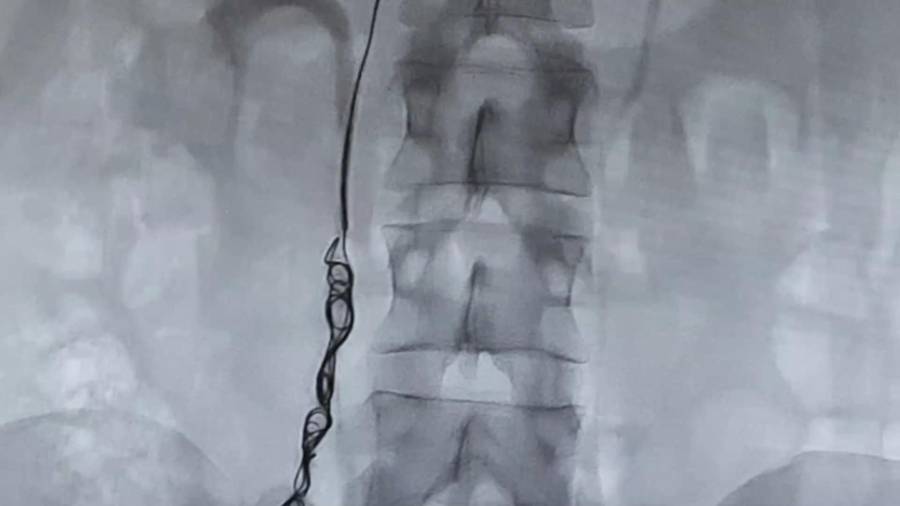

- Arteriografía

Es una técnica diagnóstica mínimamente invasiva que nos proporciona información anatómica y dinámica de las arterias, valorando posibles lesiones y permitiendo realizar el tratamiento de angioplastia en el mismo acto.

- Tratamientos arteriales

En el ámbito de los tratamientos arteriales, aplicamos endoprótesis en aneurismas, embolización arterial, stenting arterial y revascularización de estenosis arteriales. Estas técnicas de vanguardia permiten abordar las afecciones arteriales con precisión y seguridad, restaurando la circulación adecuada y preservando la función vascular.